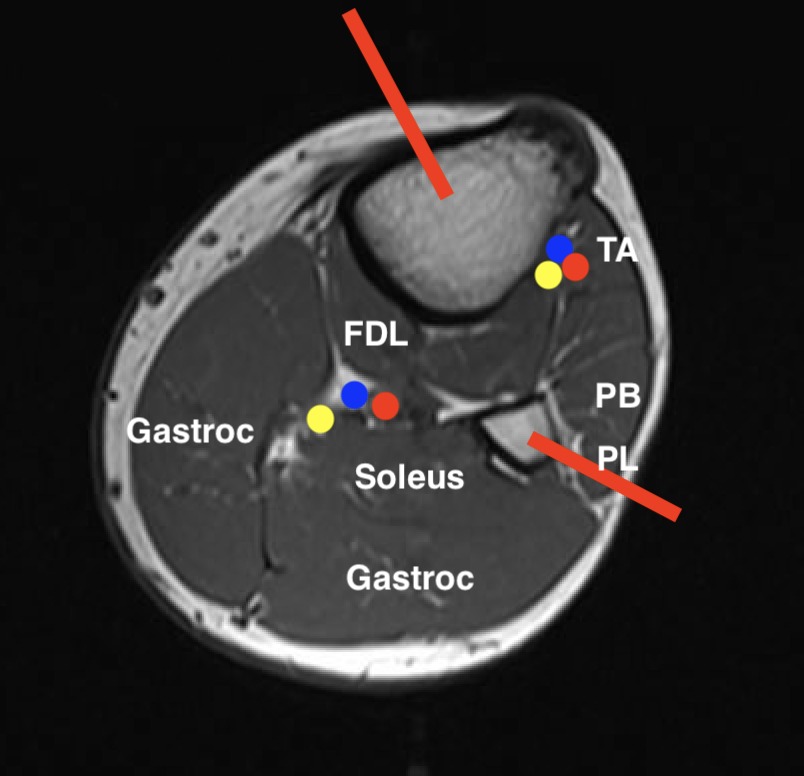

Leg

1.  Proximal posterior compartment soft tissue tumour

- medial to tibia

- preserve anterolateral compartment

2.  Proximal anterolateral compartment soft tissue tumour

- direct approach through tibialis anterior

- will likely not be able to preserve CPN